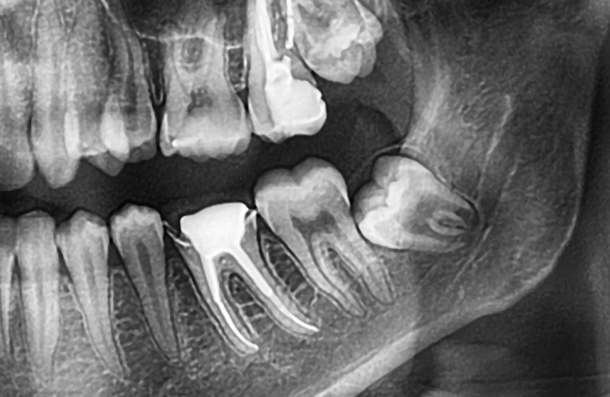

First of all, your dentist will assess your wisdom tooth and carry out an X-ray of your mouth. This gives a clearer view of the position of your teeth in order to determine if it needs to be removed.

We may request a OPG scan, at an additional cost. This is to be completed prior to the extraction appointment to assess the full position of the tooth and its proximity to the ID nerve. This is to ensure we reduce the risk of nerve injury.

An impacted wisdom tooth happens when there isn’t enough space for it to break through the gum properly. It can become twisted, tilted, or trapped in the jaw.

There are three types of impaction:

• Soft tissue impaction: The crown breaks through the bone, but part of it stays covered by gum.

• Partial bony impaction: Part of the tooth emerges, but some stays stuck in the jawbone.

• Complete bony impaction: The tooth remains fully enclosed in the jawbone.